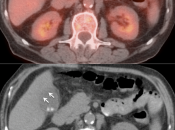

False Positives:

- Normal Physiologic Uptake

- Polyps & Adenomyomatosis

- Cholcystitis, Acute or Chronic